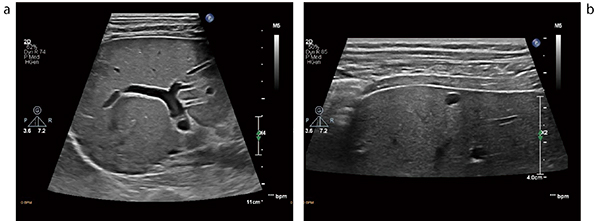

eL18-4の特長は,大きく3つに分けられる。1つ目は先述のとおり単結晶の素材を採用したこと,2つ目はカバーする周波数帯域が2〜22MHzと広いこと,そして,3つ目は多列の素子配列を採用し,ビームの厚さ方向のフォーカシング制御が可能なことである。これらの特長により,浅い部分から深い部分まで高い性能を発揮するeL18-4は,表在のみでなく腹部,消化管など幅広い領域での使用が可能になる(図2)。

図2 eL18-4の腹部画像

a:深さ11cm。50mmの口径とトラペゾイドを使用することで広い領域の描出が可能。

b:深さ4cm。肝表面における多重反射の影響が少なく,シストも認識しやすい。